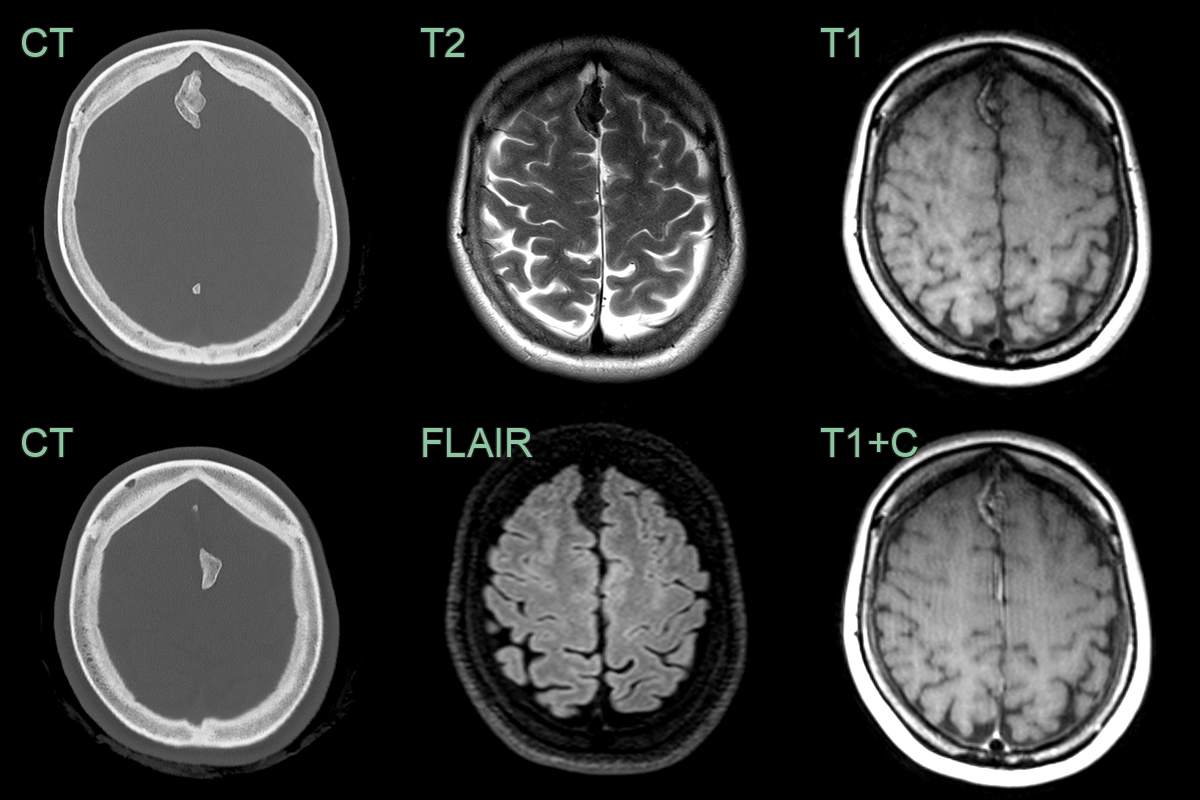

Ossification of the falx cerebri

• A 50-year-old patient presented with headache.

• CT showed lobulated calcification of both sides of the falx.

• The T1-hyperintensity and lack of enhancement was consistent with ossification of the falx (rather than a meningioma).